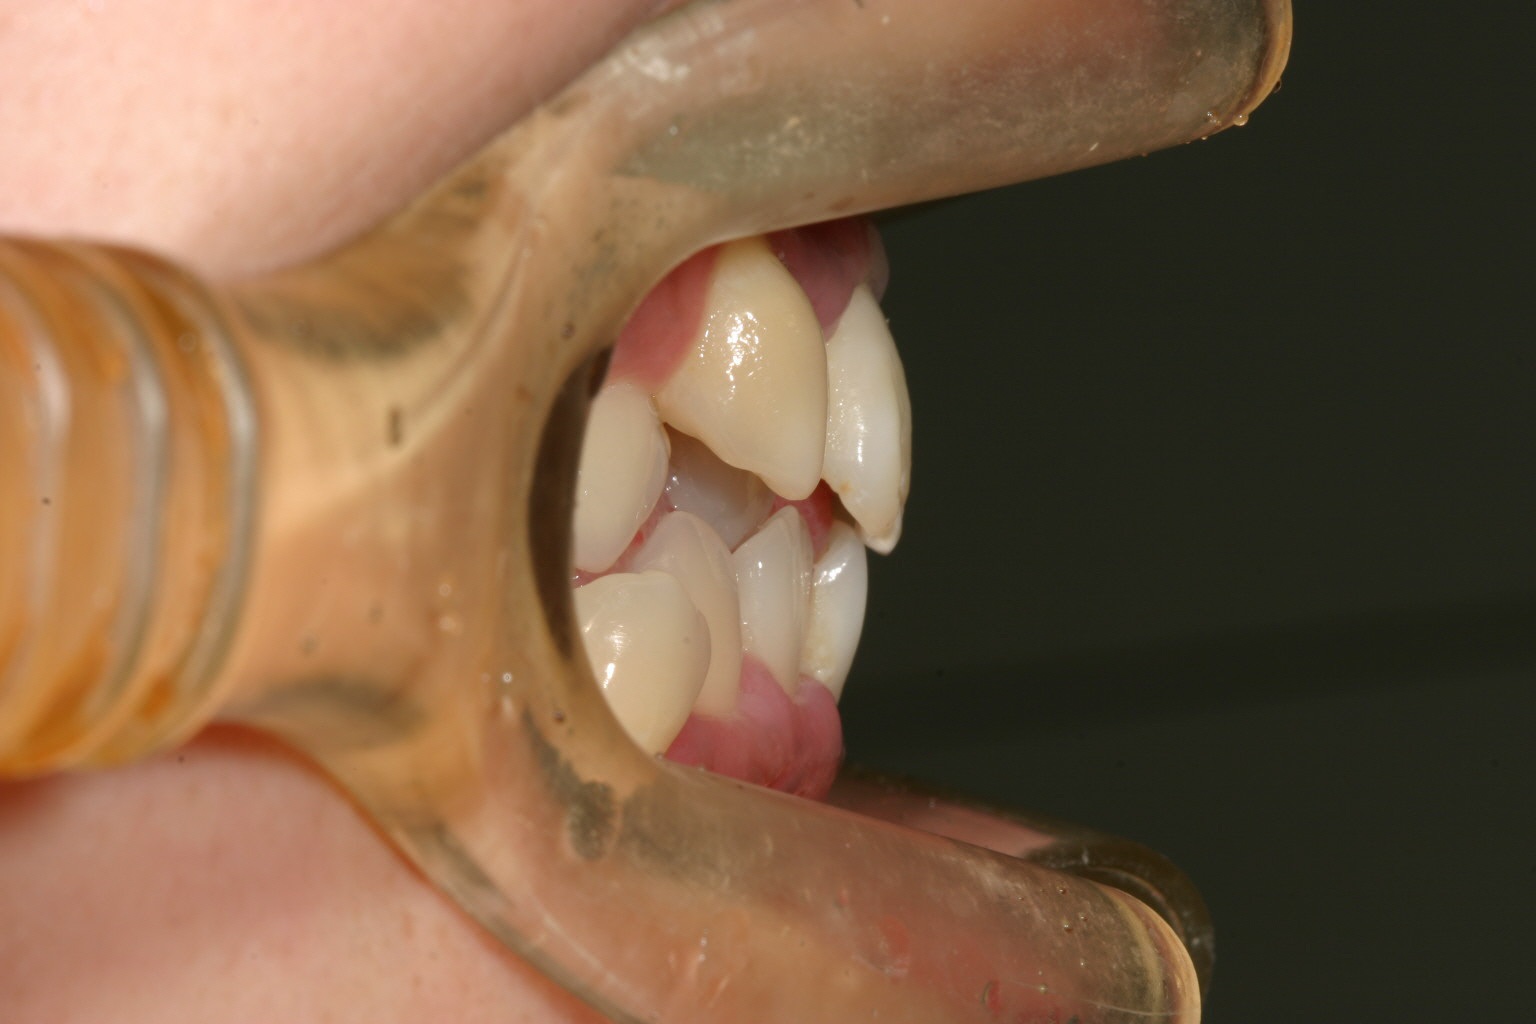

両側の八重歯が飛び出してますね!

下顎も犬歯間が狭い為に前歯がバラバラになってます。

オーバージェットはさほどでもないです。